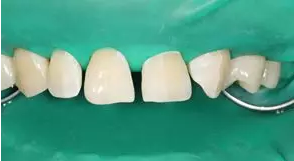

病例分享|復(fù)合樹脂微創(chuàng)美學(xué)修復(fù)關(guān)閉上前牙間隙

修形,拋光